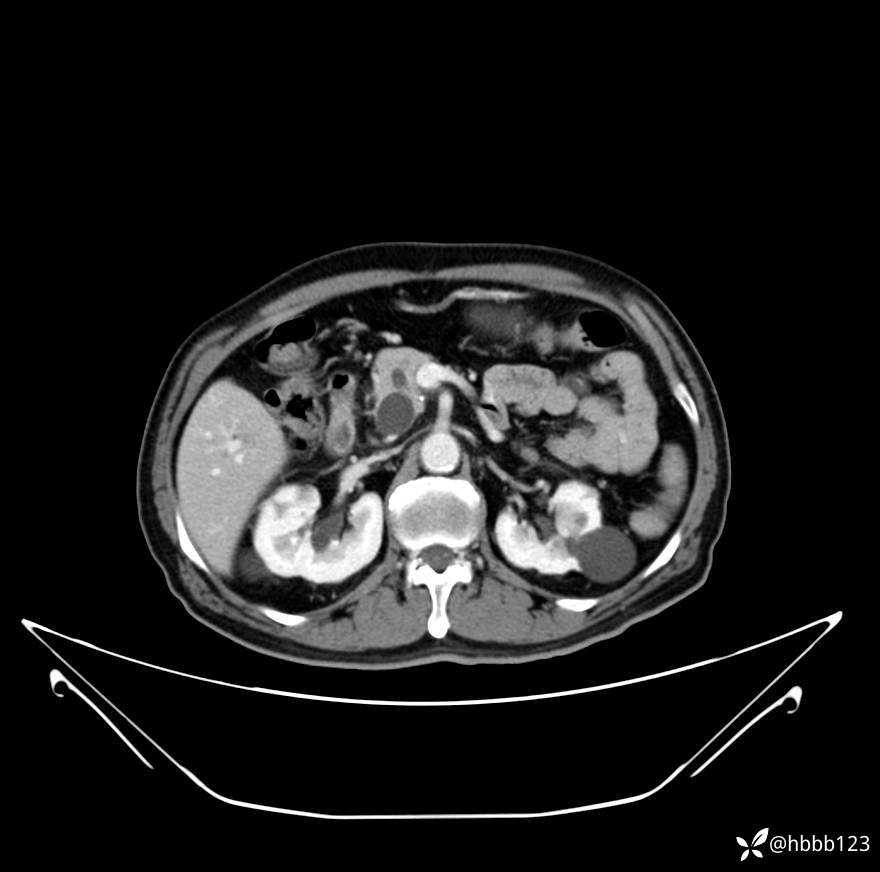

延迟期: